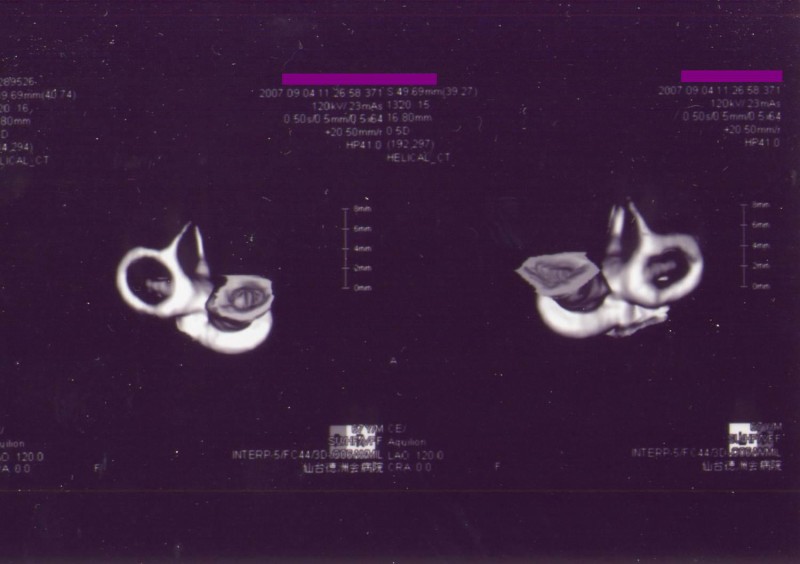

情報量を増やすために、本症例の内耳を3次元CTで立体化した画像でチェックすることにした。

Virtual Endoscope(仮想内視鏡)と称されるもので、3次元CTで右側内耳道を画像化した(図14、15)。

図14

図15